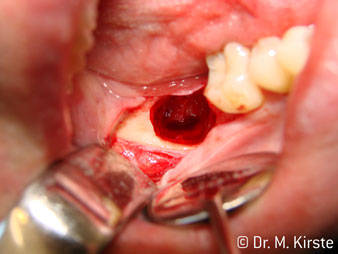

Elegir el ángulo de 45º ofrece múltiples ventajas de uso. Los odontólogos dedicados a cirugía (para quienes se desarrolló principalmente esta pieza de mano) se percatarán de inmediato de que se puede trabajar de forma muy específica. En especial en la remoción de las muelas del juicio (Fig. 2), no es necesaria una gran abducción de las partes blandas en la zona del carrillo (Fig. 3). El diseño del cabezal de la pieza de mano, combinado con los suaves giros del cabezal durante la preparación, permite trabajar de forma rápida y segura en la zona retromolar.